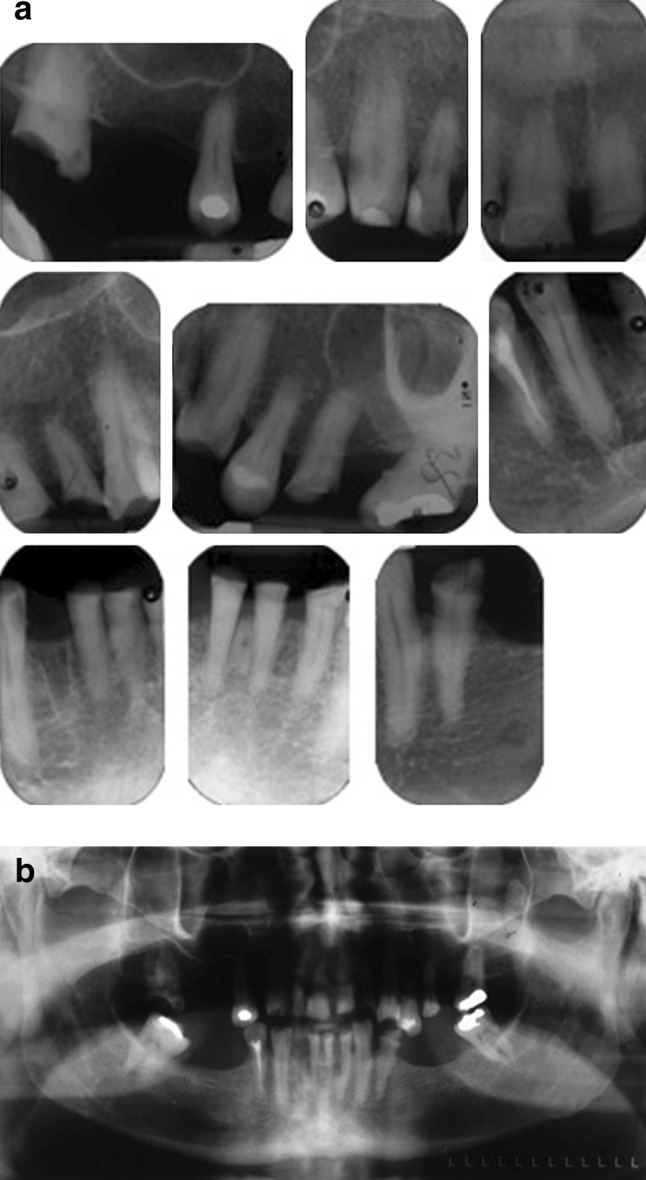

Fig. 2.

a Periapical radiographs. b Odontopantomogram